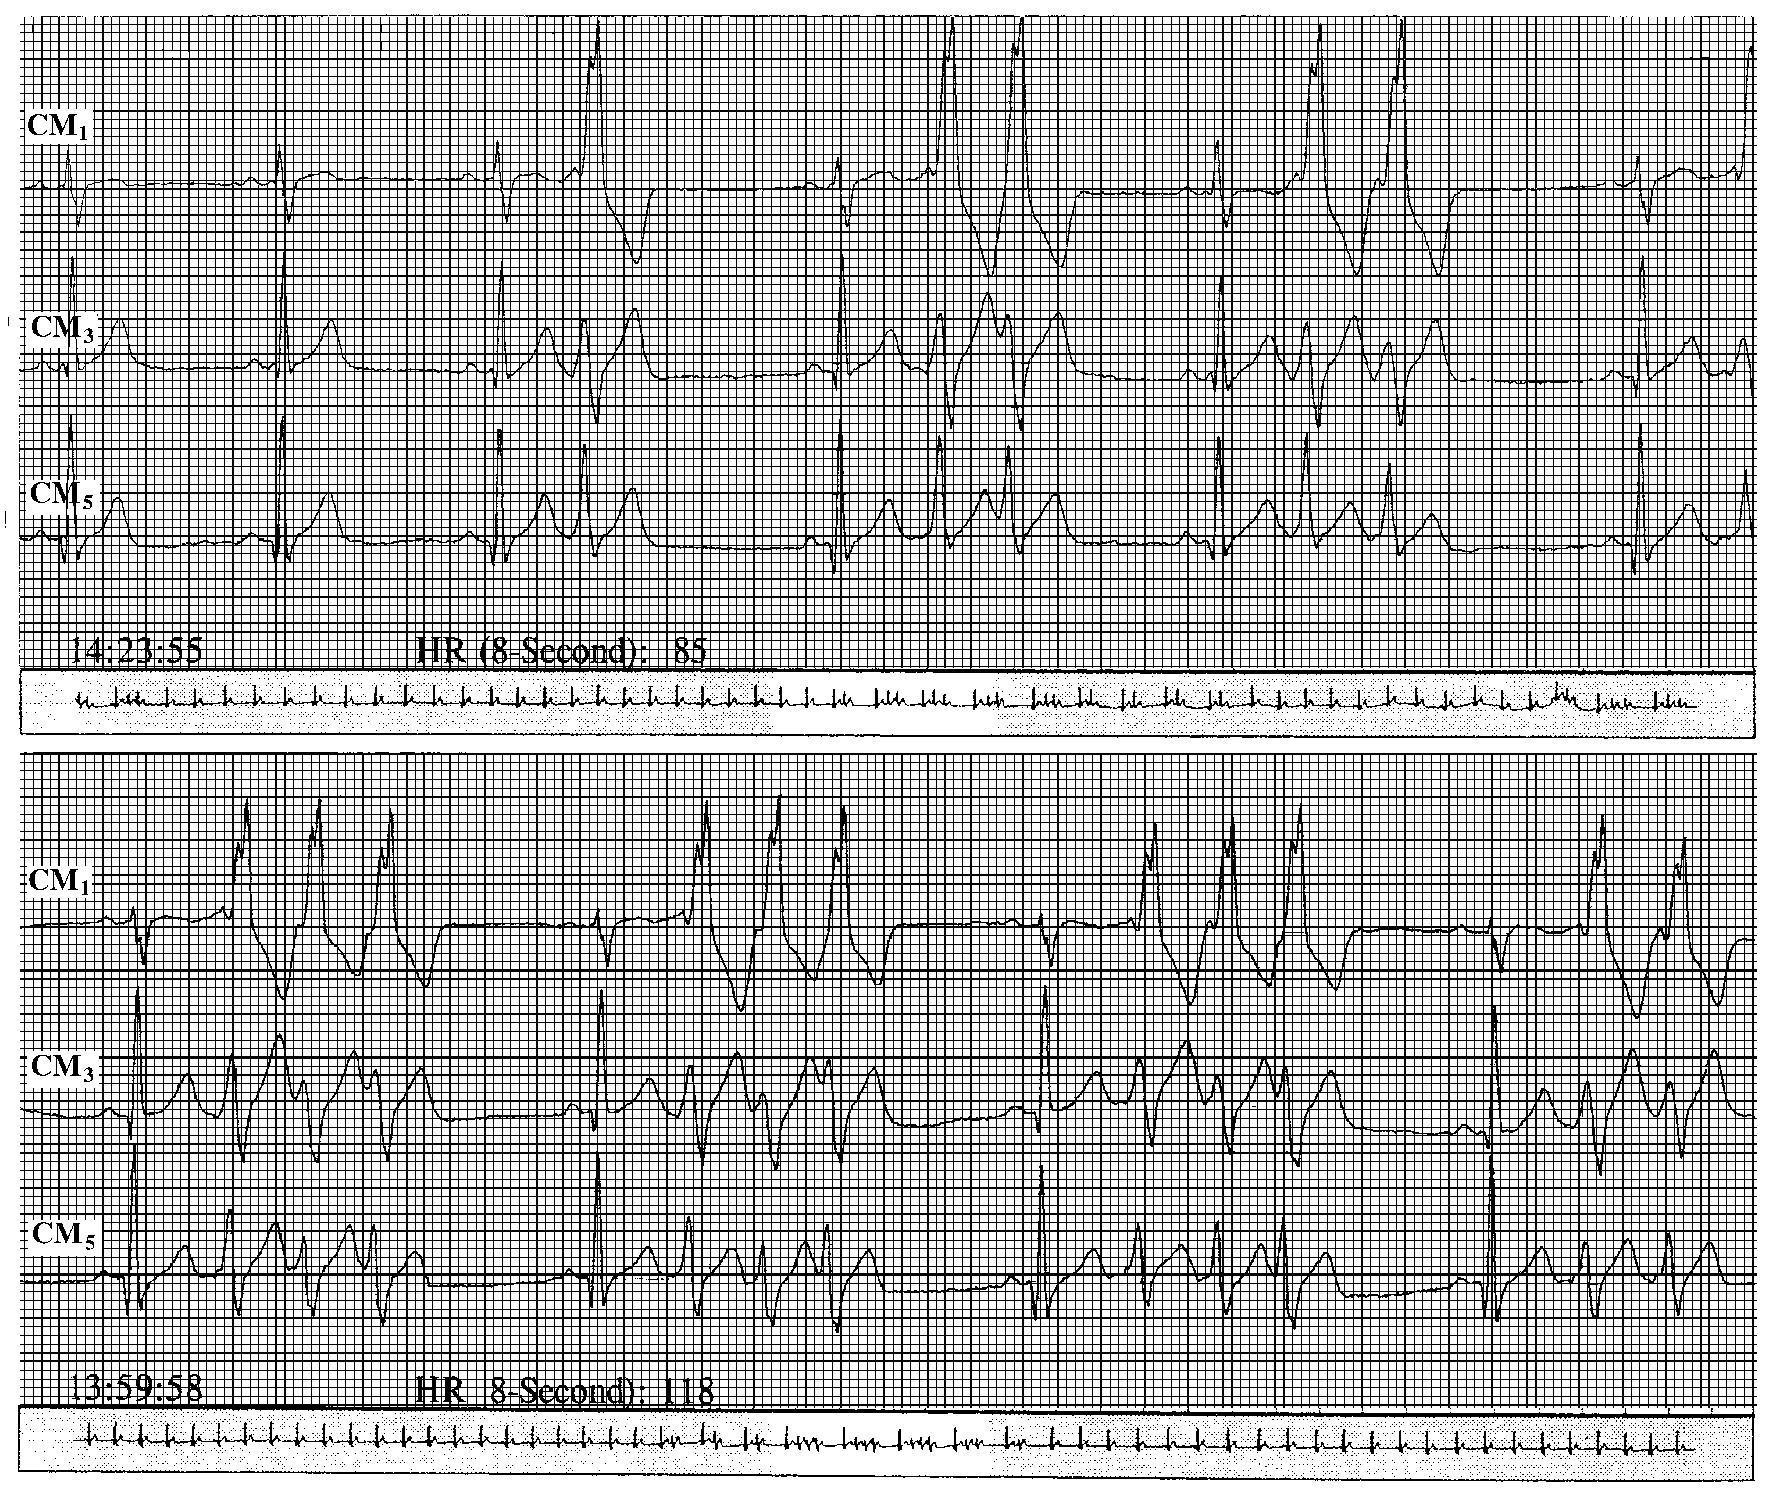

img832

图43-79 室性期前收缩终止左束支蝉联现象

男性,45岁,冠心病。心电图显示,期前收缩以前的束支传导阻滞是左束支蝉联现象引起的,发生的室性期前收缩,使双束支不应期趋向一致,左束支内蝉联现象终止